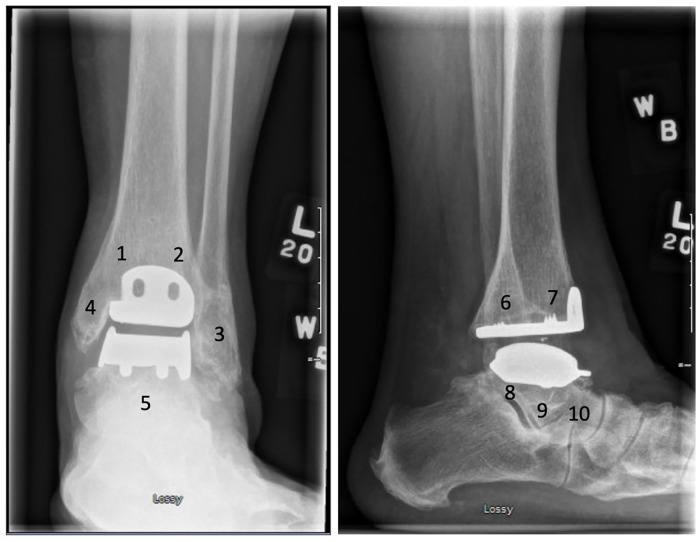

Methods: Retrospective study including all HINTEGRA TARs completed by 1 experienced foot and ankle surgeon from 2006 to 2014. Radiographs were reviewed, assessing for implant positioning, presence, location, and progression of cysts as well as relationship between osteolysis with reoperations and revisions.

Results: Fifty-one TARs were identified with radiographic follow-up of 5.8 ± 3.5 years. Eighty-four cysts were detected in 37 patients, with increasing number and size of cysts being correlated to length of time from surgery. The most common location was the posterior tibia. Thirteen patients had enlarging cysts identified over time, with the lateral malleolus being the most common location. Seven patients met criteria for malaligned prosthesis, 12 patients required a reoperation, and 2 patients experienced implant failure.